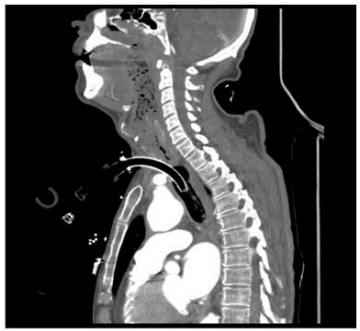

Fig 1

Imaging Findings

Emergency multiphasic CT carotid angiography using IV contrast was performed, including axial thin cuts with multiplanar and maximum intensity projection (MIP) reformatted images.

The study revealed:

• Abnormal fistulous communication between the brachiocephalic artery and the upper anterior tracheal wall, approximately 3 cm below the cricoid cartilage.

• The fistula measured approximately 5 mm in length.

• Dense secretions were noted in the trachea and main bronchi.

• Diffuse marked atherosclerotic changes were observed in the visualized portion of the thoracic aorta, characterized by mural irregularities, thickening, and intimal calcifications.

• Mild atherosclerotic changes were noted in the bilateral common carotid arteries and the extracranial segments of the internal carotid arteries, with no evidence of significant stenosis.

Figure 1